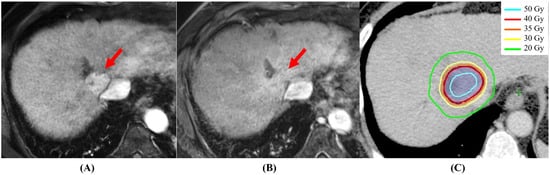

There are several unresolved issues in SBRT in early-stage HCC. The first issue is the timing of response evaluation. The evaluation method for SBRT is usually judged by whether there is early arterial enhancement of the tumor using dynamic enhanced CT or MRI [25][26][25,26]. According to the Modified Response Evaluation Criteria in Solid Tumors (mRECIST), a complete response (CR) was defined as the “Disappearance of any intratumoral arterial enhancement in all target lesions” [25]. However, this intratumoral arterial enhancement may be prolonged over 6 or more months in several cases, and this fact confuses the timing of response evaluation. In a previous report, Kimura et al. evaluated the patterns of dynamic enhanced CT appearance of tumor responses after the completions of SBRT. They observed residual early arterial enhancement in 19 lesions (28.4%) more than 3 months after SBRT in 59 patients with 67 tumors [27]. Based on this result, researchwers propose that the response evaluation at 6 months, not at 3 months, after the completion of SBRT is the appropriate time point, because in most cases there was ab observed disappearance of residual early arterial enhancement within 6 months. Figure 1 shows a typical case of CR at 3.5 months after the completion of SBRT. The second issue is the optimal dose-fraction schedule. The several dose-fraction schedules are shown in Table 1. Kim et al. analyzed the dose–response relationship in a multi-institutional retrospective cohort that included 510 patients treated with SBRT [28]. Patients treated with a biological effective dose (BED) ≥ 100 Gy showed a better 2-year freedom from local progression (FFLP) and OS than did patients treated with a BED < 100 Gy (FFLP, 89% vs. 69%; OS, 80% vs. 67%; p < 0.001). In addition, a multivariate analysis before and after propensity score-matching (PSM) in 198 selected patients between BED ≥ 100 Gy and BED < 100 Gy, identified BED ≥ 100 Gy as the main prognostic factor for both FFLP and OS (p < 0.01). Higher dose-fraction schedules may improve LC and OS. The third issue is the combination with TACE. Kimura et al. compared SBRT alone (28 patients) with SBRT+TACE (122 patients) in small HCC, the median tumor size was < 20 mm, retrospectively [29]. The 2 year OS and local progression-free survivals (LPFS) for SBRT alone and SBRT+TACE groups were 78.6% and 80.3% (p = 0.6583) and 71.4% and 80.8% (p = 0.9661), respectively. On the other hand, Su et al. also compared SBRT alone (50 patients) with SBRT+TACE (77 patients) in large HCC, with median tumor size being 85 mm, retrospectively [30]. The 5 year OS was significantly higher in the SBRT + TAE/TACE group (46.9%) than that in the SBRT alone group (32.9%; p = 0.049). The LPFS did not differ significantly between the two groups. These opposite results suggested that the combination of SBRT and TACE has the potential to improve treatment results, compared with SBRT alone, especially in patients with larger HCC, such as those of >5 cm, but SBRT alone could be a significant treatment option for patients with small HCC, such as those of <2 cm. To resolve these issues, further prospective studies are warranted.

Figure 1. A typical case of complete response at 3.5 months after the completion of SBRT. (A) Dynamic MRI appearance (arterial phase) before SBRT; the early arterial enhancement is obvious (red arrow). (B) Dynamic MRI appearance (arterial phase) after 3.5 months; the early arterial enhancement has disappeared (red arrow). (C) Dose distribution of SBRT: the prescribed dose of 40 Gy covered 95% of PTV with 125% maximum dose of 40 Gy (80% isodose) in 4 fractions.